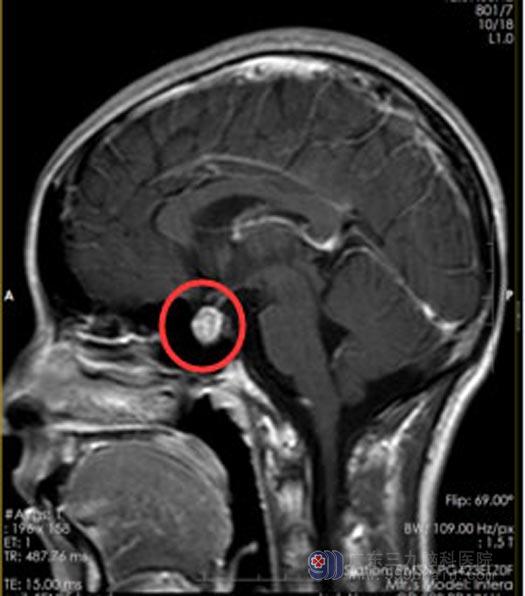

结合各项检查结果和小莹的症状体征,考虑是分泌型垂体瘤,这种垂体瘤一般首选药物治疗,小莹也选择了口服药物治疗。不久前,小莹突然觉得头痛,返院复查头颅MR,提示:垂体大腺瘤囊变,出血可能性大,较前范围有所增大,结节影大小有18mm×10mm×15mm。外五科的治疗团队经过讨论,一致认为小莹现在的情况具有手术指征。